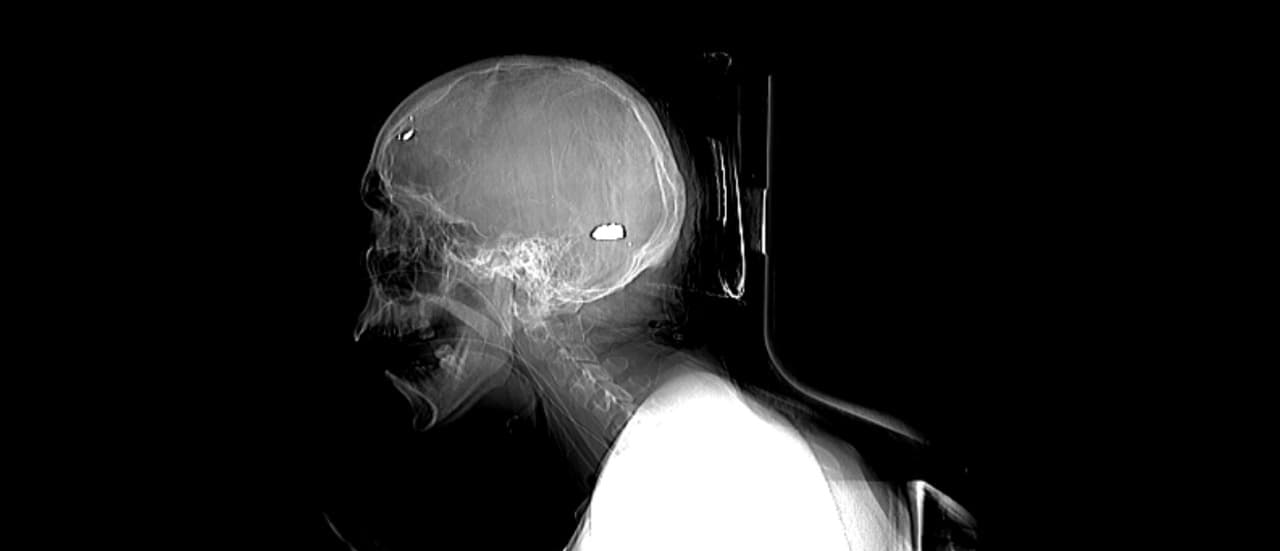

Autopsy reports examined by the IACHR from staff at public hospitals found “numerous victims were treated for bullet wounds in the head, eyes, neck and the thorax, as well as in the back. The mechanics and trajectory of the shots would indicate arbitrary use of lethal force, or extrajudicial executions.”

During the assault, one of the local resistance leaders Darwin Potosme, 33, was standing at a street barricade with a home-made mortar when he was struck in the eye by a bullet that shattered his skull. When one of his closest companions came to the rescue and tried to lift his body he also came under fire, hit by a bullet that went clean through his cheek.